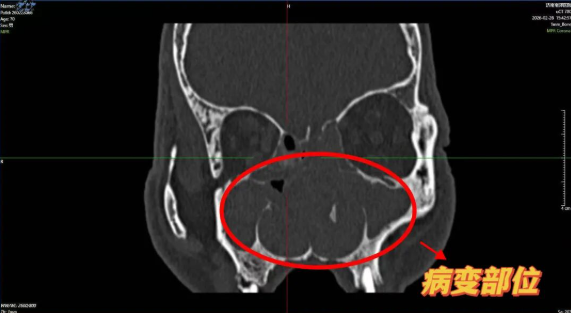

耳鼻喉科杨钦龙主任详细询问病史,结合触诊与鼻内镜检查,发现其双侧鼻腔布满息肉样组织,中鼻道及嗅裂被完全堵塞,多个鼻窦存在炎症积液,诊断为“慢性鼻窦炎伴鼻息肉、鼻中隔偏曲”。考虑到患者高龄、基础病多且长期缺氧影响全身状态,杨主任团队为其制定了“鼻内窥镜下多鼻窦开窗+鼻息肉切除”的微创方案,既能彻底清除病灶,又能最大限度保护鼻腔功能。

手术在杨主任丰富的临床经验,在鼻内镜高清视野下精准定位病变范围中精确完成。术后第二天,张大爷便觉呼吸通畅,久违的清新空气让他激动地反复摸索着说:“通了!通了!”